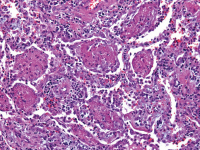

DAD - EVALI

Abbildung 2: Diffuse Alveolenzerstörung (DAD) bei einem Patienten, der durch EVALI gestorben ist (H & E, Bar 20 μm).

Keywords: DADEVALIHistologisches Präparat